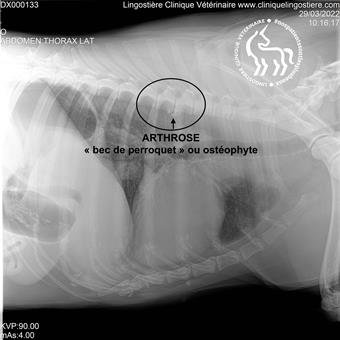

Arthrose chez le chien

L’arthrose est une maladie fréquente chez les animaux âgés, mais elle peut également toucher les plus jeunes. Elle se caractérise par une dégénérescence du cartilage entourant les articulations, ce qui peut provoquer de la douleur, de la raideur et une réduction de la mobilité de votre animal. Les articulations touchées les plus courantes sont les hanches, les épaules, les genoux et les coudes.